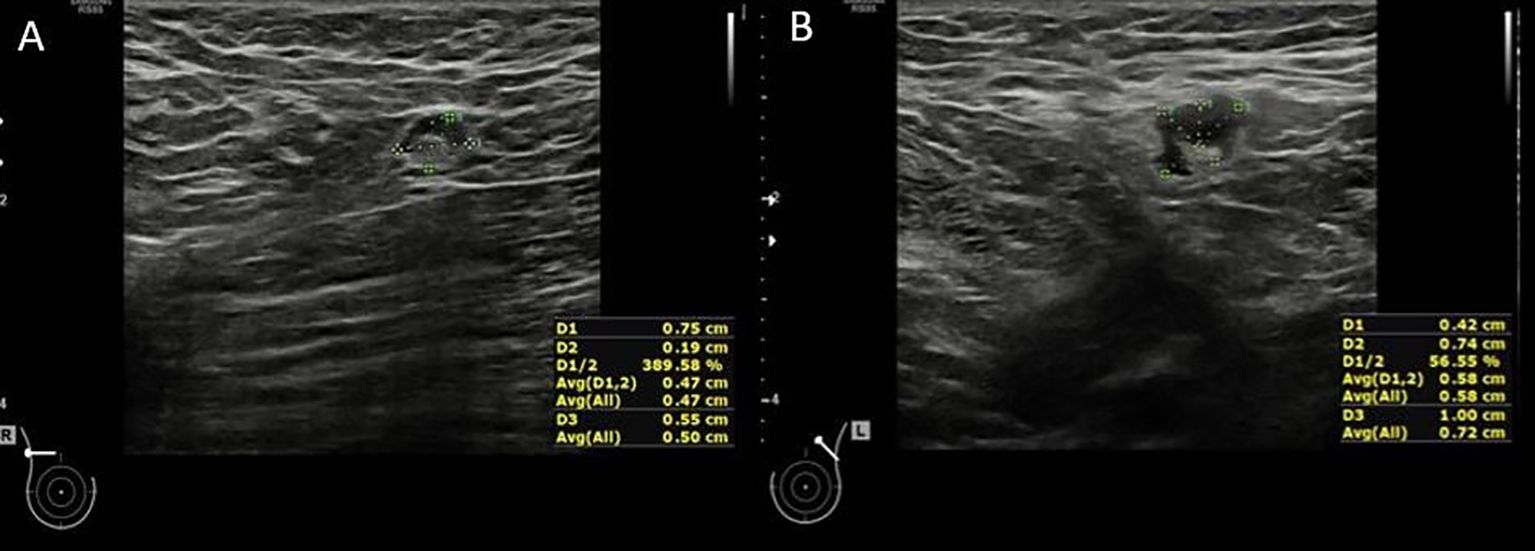

Background: Accurate axillary lymph node assessment is critical in breast cancer staging. This study aimed to evaluate whether ultrasound (US)-based measurements, particularly cortical thickness and comparison with contralateral lymph nodes, could improve diagnostic accuracy in detecting axillary metastasis. Methods: In this prospective study, 110 breast cancer patients underwent bilateral axillary US. Ipsilateral and contralateral lymph nodes were assessed for shape, size, cortical characteristics, and hilum preservation. Quantitative features were compared between metastatic and non-metastatic nodes. Diagnostic accuracy was evalu-ated using ROC analysis, and various cut-off values were tested. Results: Metastatic nodes showed significantly increased cortical thickness (median 7.5 mm vs. 2.1 mm, p<0.001), larger short axes, and irregular shapes. The cortical thickness of ipsilateral lymph nodes had an AUC of 0.967 with a 3.4 mm cut-off yielding 97.7% sensitivity and 89.1% specificity. Comparing ipsilateral and contralateral cortical thickness revealed a 2.05 mm difference as optimal (AUC 0.926, 86% sensitivity, 89.1% specificity). US-based assessment outperformed traditional imaging in accuracy (92.66% vs. 82.73%). Conclusions: Quantitative US assessment of axillary lymph nodes, especially cortical thickness and bilateral comparisons, enhances diagnostic accuracy in breast cancer. Integrating these measures may reduce unnecessary biopsies and improve staging efficiency.